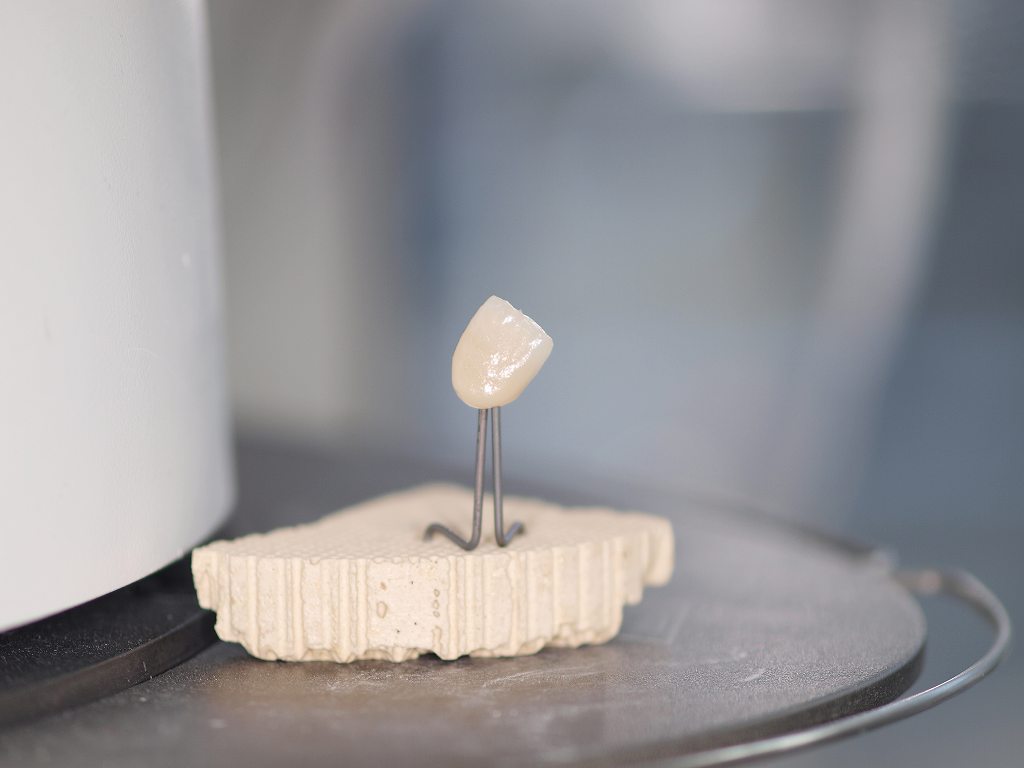

前歯部のセラミッククラウンにはジルコニアクラウンとオールセラミッククラウンの2通りが存在します。 オールセラミッククラウンはe-maxといわれるイボクラ社のガラス系二ケイサンリチウムをフレームとして使用していき、レイヤリングの形態をとります。|お知らせ |広島市安佐南区の歯科医院

前歯部のセラミッククラウンにはジルコニアクラウンとオールセラミッククラウンの2通りが存在します。 オールセラミッククラウンはe-maxといわれるイボクラ社のガラス系二ケイサンリチウムをフレームとして使用していき、レイヤリングの形態をとります。

前歯部のセラミッククラウンにはジルコニアクラウンとオールセラミッククラウンの2通りが存在します。 オールセラミッククラウンはe-maxといわれるイボクラ社のガラス系二ケイサンリチウムをフレームとして使用していき、レイヤリングの形態をとります。